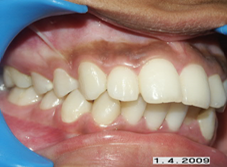

Pre prosthetic treatment

The replacement of teeth which are missing due to extraction or other reasons require some Orthodontic treatment to align the remaining teeth so that the replacement teeth can be favorable placed.

Replacement of Teeth made possible due to Orthodontic Treatment